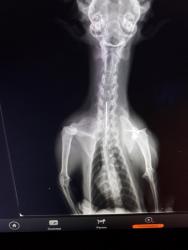

В ветеринарную лечебницу № 1 обратилась женщина, чья кошка сильно кашляла. По словам хозяйки, животное прошло курс лечения в другой клинике по поводу бронхопневмонии, но так и не выздоровела. В ходе диагностики был сделан снимок, на котором было ясно видно, что в мягких тканях шейно-грудного отдела между пищеводом и трахеей находилась игла.